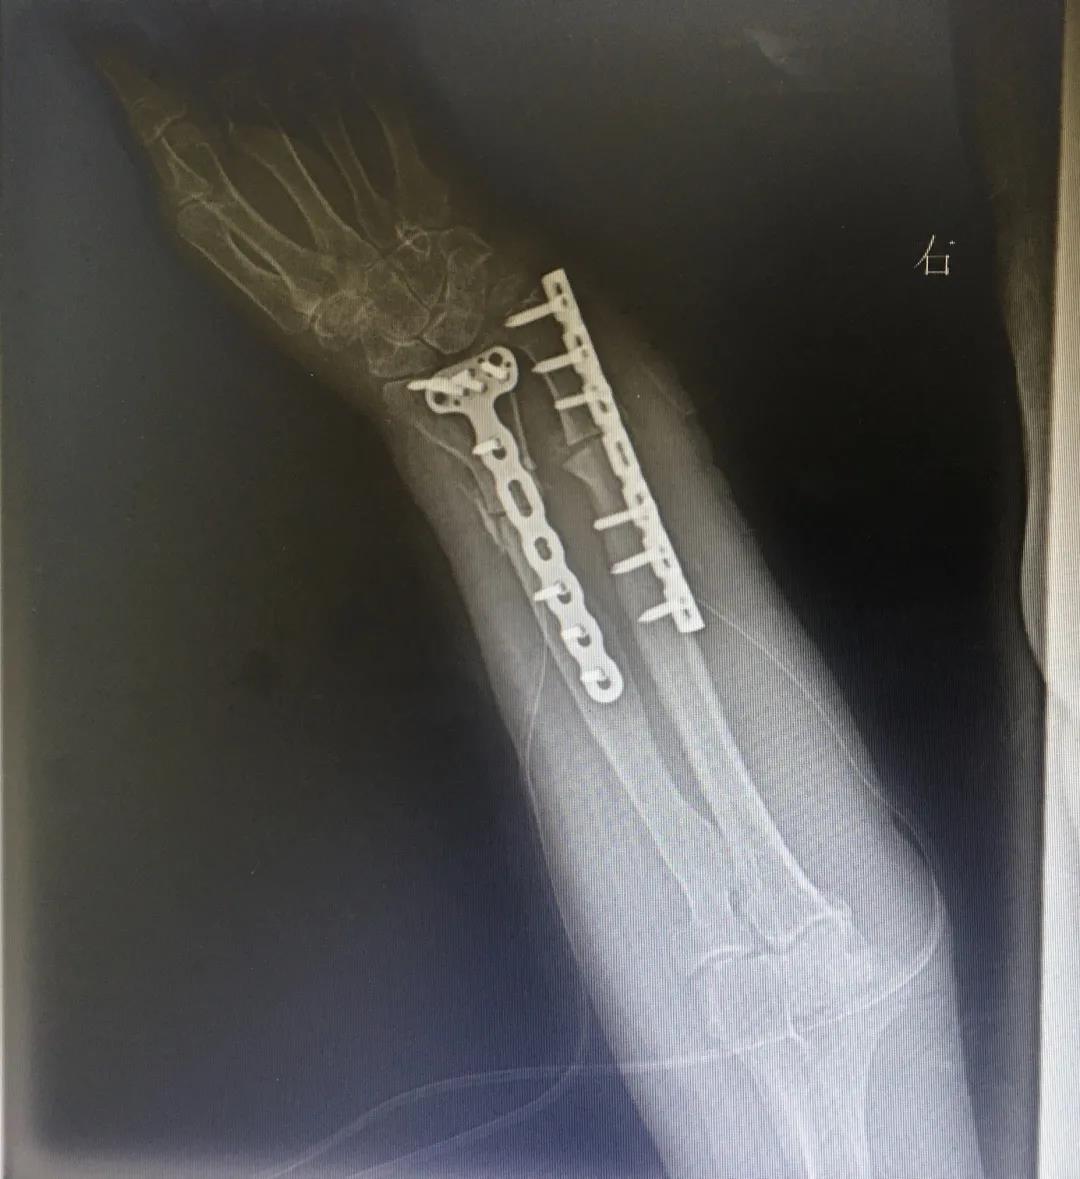

今年7月上旬,阿婆的右臂不慎再次受伤。子女们将她送到了乐清友义骨伤医院。医生诊断其“外伤性右尺桡骨下段陈旧性骨折,伴假关节形成”。门诊以“右尺桡骨陈旧性骨折”收住入院。

7月中旬,乐清友义骨伤医院骨科王临主任团队为阿婆的假关节施行了“右尺桡骨切开截骨矫形+植骨钢板内固定术”。

手术非常成功,目前恢复良好。再过2天,阿婆就可拆线出院了。

手术前

手术后